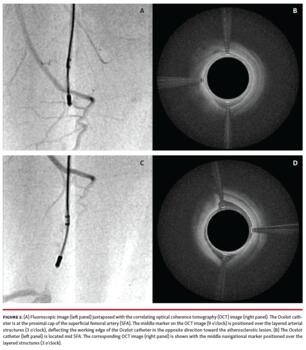

The patients were prepared for surgery following standard procedures. The target lesion was identified by angiography and its length was documented. With the lesion identified, the occlusion was traversed with an Ocelot crossing catheter (Avinger) (Figure 2) and then subsequently treated with TurboHawk directional atherectomy (Medtronic). Excised tissue was captured in the nosecone of the atherectomy device and collected at the end of the procedure, fixed in 10% neutral buffered formalin following standard methodology, and sent to the pathology lab.

A total of 19 patients participated in this pilot phase of the HIPACT study; they were predominantly male (67%) with a mean age of 72 ± 11.6 years. The CTO lesions were primarily (67%) in the superficial femoral artery (SFA), with 4 in a popliteal artery, and 1 each in the tibial peroneal trunk and the common iliac artery. All obstructions were crossed successfully by the crossing catheter with no dissections or perforations. Directional atherectomy reduced the obstructions such that blood flow was restored through the area of the obstruction, as determined by angiography. The amount of fluoroscopy time varied with the device used, with less than a minute of time (14 seconds) needed when the OCT-guided catheter was advanced through the obstruction to prepare a path for the atherectomy device (Figure 3).

In this study, the catheter used to cross the CTO has the capability of providing intravascular imaging via OCT on its cannula. This resulted in successful crossing in 100% of CTOs, and it was possible to maintain the cannula of the device within the center of the lumen of the vessel by monitoring the advancement of the catheter with its OCT imaging. Trauma to the vessel wall during CTO crossing has been associated with inflammatory cascades and can serve as a nidus for restenosis. In addition, the atherectomy device used in this study is guided by and monitored with angiography, which makes it a challenge to determine how deeply one is cutting into the layered structures of a peripheral artery during atherectomy. Use of an OCT-guided atherectomy catheter has been noted to result in low TLR rates at 6 months.